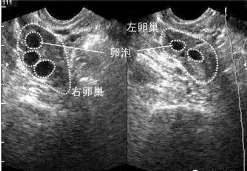

查看全文试管婴儿技术是目前治疗不孕不育疾病最为有效的一种助孕手段,目前国内有接近20%的人群均患有不同程度的不孕不育疾 […]